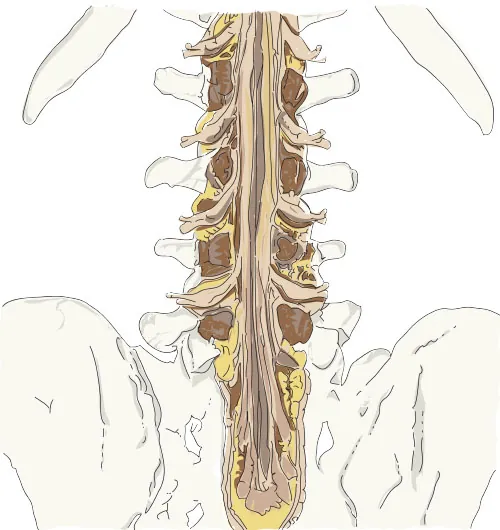

As the vertebral column grows, these nerves grow with it and result in a long bundle of nerves that resembles a horse’s tail. This is named the cauda equina (Figure 23.8).

The image is an anatomical illustration showing a detailed view of the lower part of the spinal cord, specifically the cauda equina. The illustration highlights the bundle of spinal nerves and nerve roots extending from the lower end of the spinal cord. The surrounding vertebrae and pelvis bones are also depicted, providing context for the location of the cauda equina within the body. The spinal nerves are shown in yellow, while the vertebrae and bones are illustrated in neutral tones. This detailed view emphasizes the complexity and structure of the cauda equina within the lumbar spine region.

Figure 23.8 The bundle of nerve roots located at the end of the spinal cord is called the cauda equina because it resembles a horse’s tail. (credit: “Cauda Equina” by Daniel Donnelly/Flickr, CCBY 4.0)